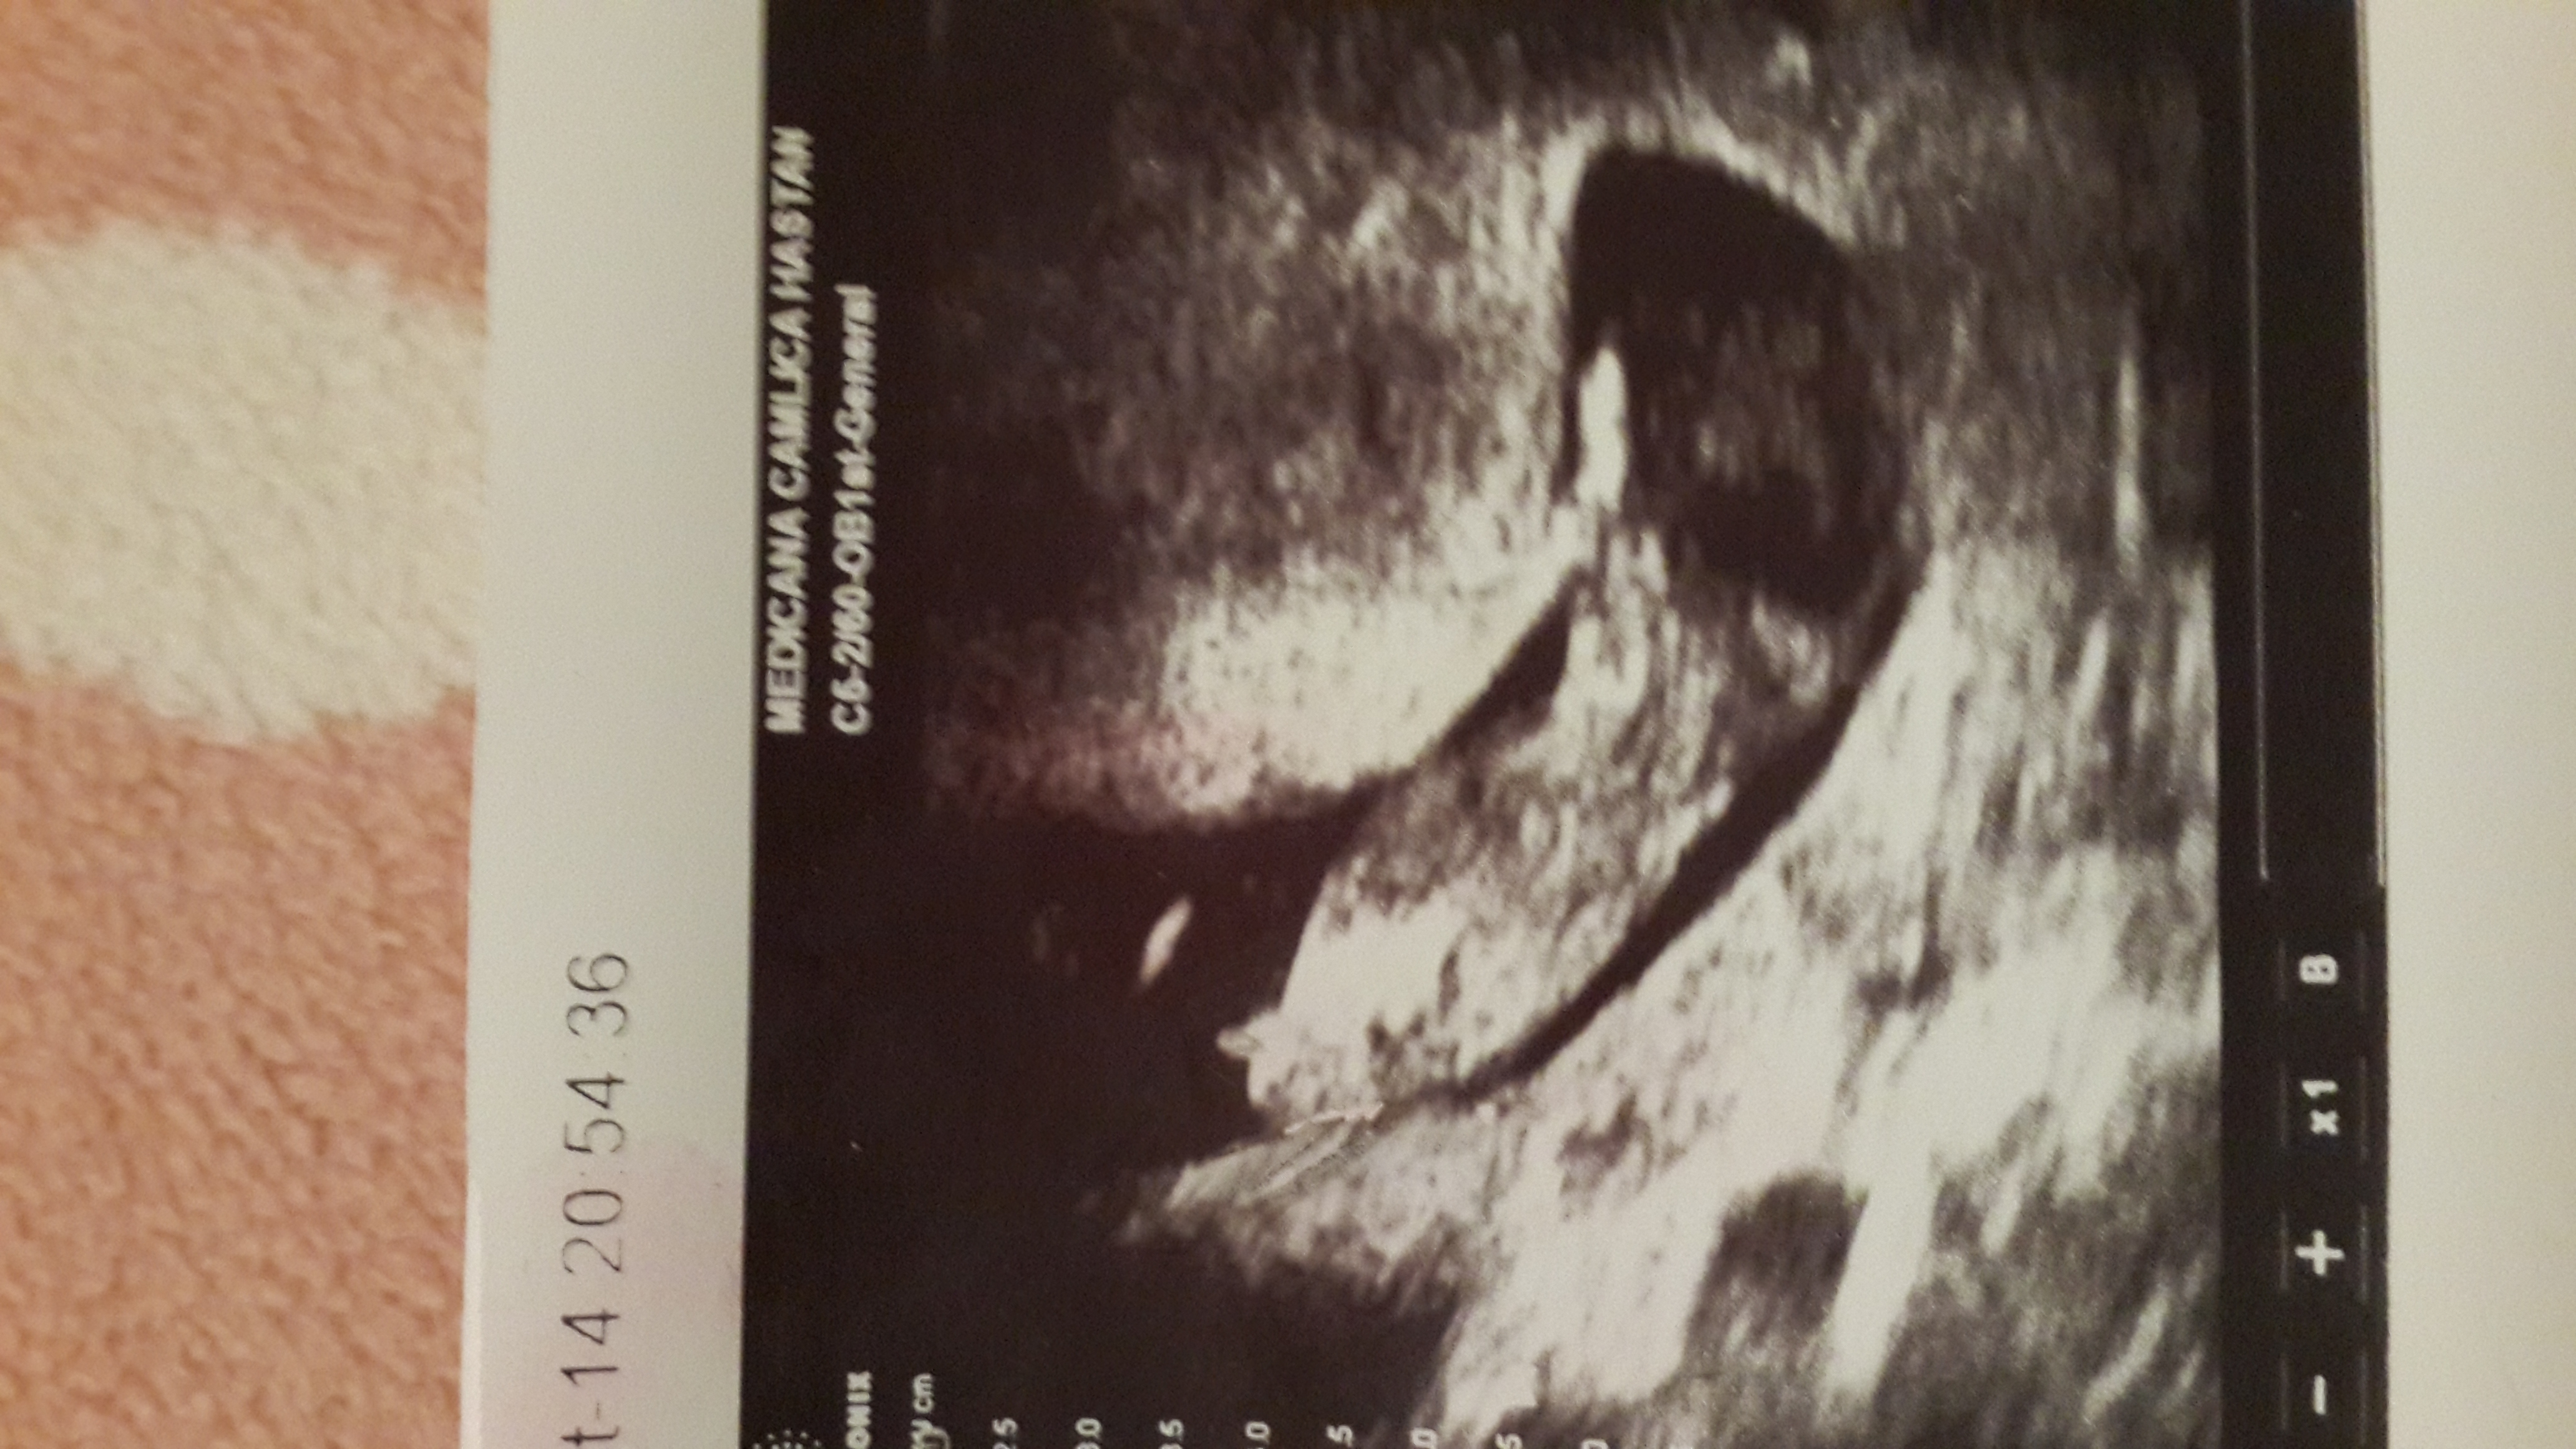

Unfortunately i have no another picture like this position..12w+2 us in here please guess my baby's gender

Many thanks in advance.Attachment 21883

leaning blue

Really can't make out anything on this pic, shame they never gave you anything more useful :/ x

Thinking boy.

boy lean

Boy x